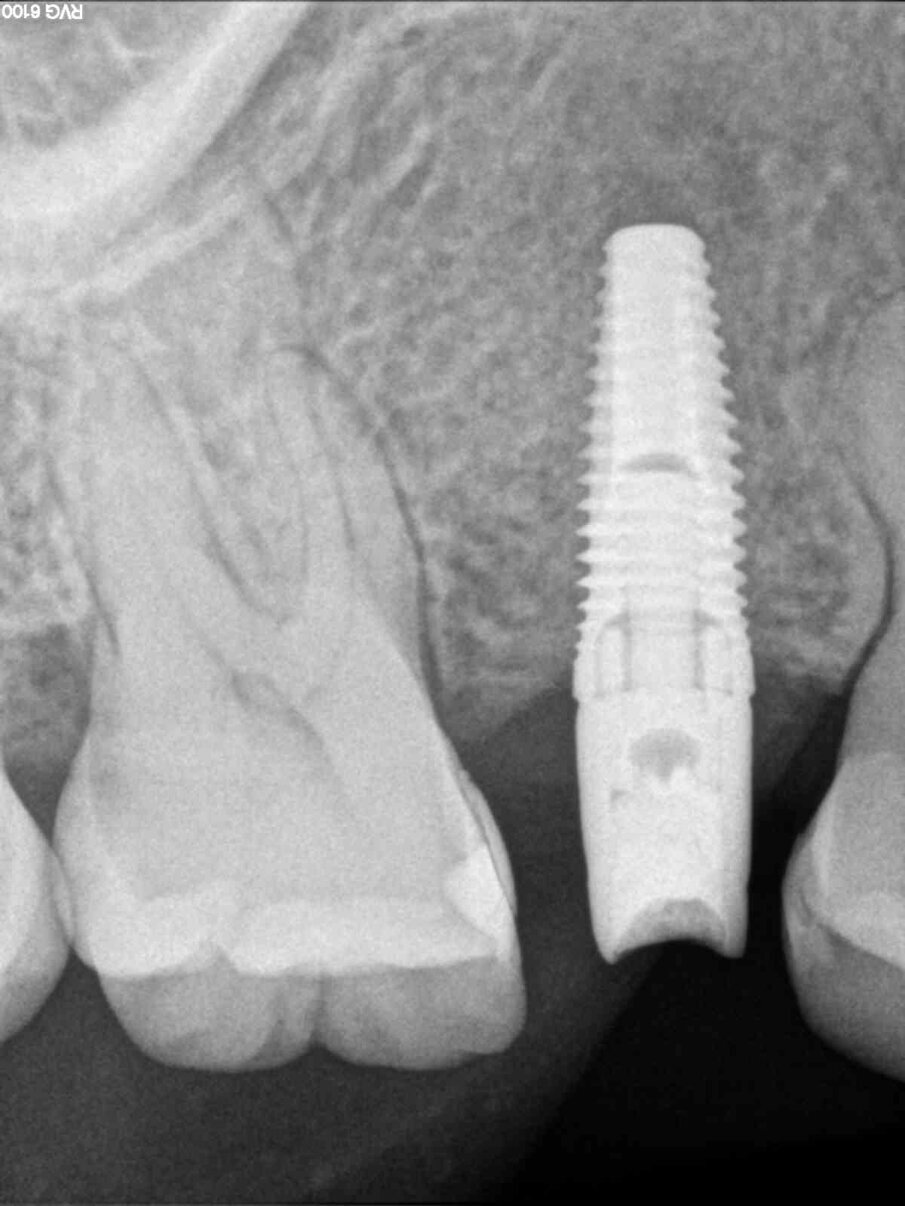

Viene inserito nel centro della cresta neoformata un impianto osteointegrato Neoss Tapered 4.0 x 13 mm con torque di inserimento di 60 Ncm e ISQ 80 (Figg. 22-24). La rigenerazione ossea crestale permette di inserire l’impianto in una posizione protesicamente guidata e con 2 mm di tessuto osseo vestibolare; questa situazione migliora la prevedibilità della riabilitazione implanto-protesica29-33. Dopo 2 mesi di provvisorizzazione si cementa il manufatto protesico definitivo (Figg. 25-28). Il controllo clinico e radiologico a 6 anni (Figg. 29, 30) mostra la stabilità dei tessuti molli e dell’osso perimplantare. Il confronto tra baseline e 6 anni dalla riabilitazione protesica evidenzia la stabilità nel tempo della rigenerazione volumetrica crestale (Fig. 31).

Fig. 22 - Impianto Neoss inserito al centro della cresta ossea.

Fig. 23 - ISQ di inserimento dell’impianto - 80.

Fig. 24 - Radiografia dopo connessione abutment definitivo.